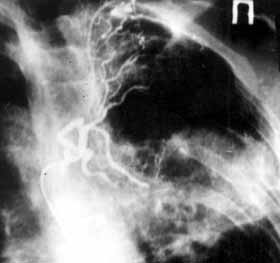

Рис. 3. Эмболизация правой бронхиальной артерии при неоперабельном раке легкого, осложненном кровохарканьем. (Слева) На снимке до эмболизации определяется гиперваскулярная опухоль правого легкого, явления экстравазации. (Справа) После эмболизации - отсутствие кровотока в опухолевых сосудах. "Культя" ветвей бронхиальной артерии.